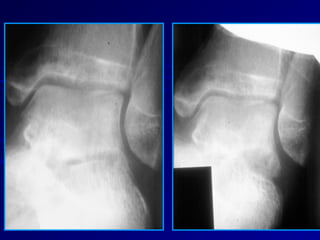

Subtle Fractures MimickingSubtleFractures Mimicking InstabilityInstability Anterior Process of the calcaneusAnterior Process of the calcaneus  Commonly over-lookedCommonly over-looked  Pain located anterior to ligamentsPain located anterior to ligaments  Small – exciseSmall – excise  Large – ORIFLarge – ORIF

Talus FracturesTalus Fractures LateralProcess FracturesLateral Process Fractures  24% of talus fractures24% of talus fractures  Snowboarders fractureSnowboarders fracture  Dorsiflexion, compression, and ext. rotationDorsiflexion, compression, and ext. rotation  Serves as insertion point for many ligamentsServes as insertion point for many ligaments  Often overlookedOften overlooked  Involves fibula and calcaneusInvolves fibula and calcaneus

Talus FracturesTalus Fractures LateralProcessLateral Process FracturesFractures  Confused with lateralConfused with lateral ankle sprainsankle sprains  Evaluator needs toEvaluator needs to remain awareremain aware  Seen on plain filmsSeen on plain films  CT to determine sizeCT to determine size and typeand type

Talus FracturesTalus Fractures LateralProcess FracturesLateral Process Fractures  TreatmentTreatment Non-displacedNon-displaced  4 weeks SLC non-weight bearing4 weeks SLC non-weight bearing  2 weeks in SLWC2 weeks in SLWC DisplacedDisplaced  Depends on sizeDepends on size  Excise if to smallExcise if to small  Fixate in large enoughFixate in large enough